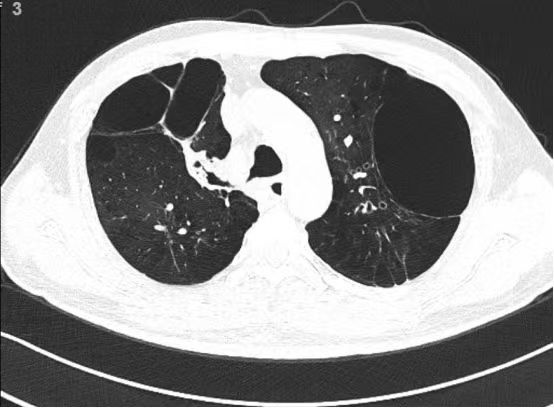

48岁的王先生因自述“反复咳嗽咳痰、气喘二十余年,加重一周”,于2月14日慕名到院治疗。过去二十年间,他因严重气喘无法远行,日常步行百米即需停歇,活动范围仅限小区花园。CT检查显示其双肺上叶存在巨大肺大泡,严重挤压正常肺组织,导致肺功能急剧下降。

2月26日,呼吸与危重症医学科行政主任刘祁汨采用肺叶通气功能检测系统,精准评估患者右肺上叶及左肺上叶支气管通气功能。为兼顾疗效与经济性,团队创新设计“分步疗法”:首阶段实施右肺上叶前段支气管活瓣置入,待靶区肺大泡充分萎陷后取出活瓣,再根据疗效评估选择适宜区域进行二次置入,最大化减少手术费用。